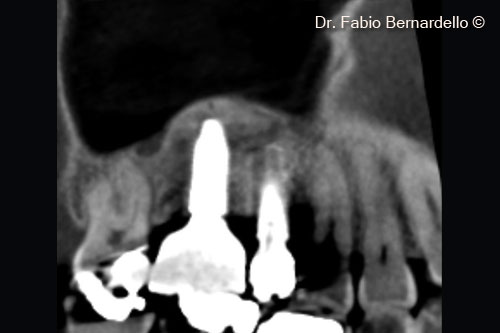

Ảnh chụp X-Quang trước phẫu thuật. Một trụ Implant đã được cấy ghép để thay thế răng số 16 khoảng 10 năm trước

Cấu trúc xoang hẹp ( Chiều rộng < 12mm khi đo ở vị trí cách sống hàm trên 10mm) chiều cao xương còn lại từ 3 mm đến 5 mm cho phép thực hiện phẫu thuật 1 thì. Nâng xoang hàm và cấy ghép implant theo vị trí.

Hình ảnh CBCT mặt cắt ngang tại thời điểm ban đầu (T0). Gel 40 nâng màng xoang tại vị trí cấy ghép mới và cả phía trên đỉnh của implant cũ ở vị trí số 16